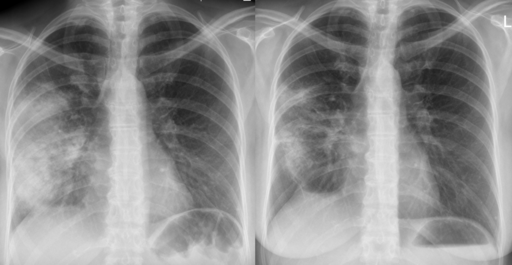

Chest X-ray

A definitive diagnosis of CAP requires evidence of consolidation on a chest x-ray (CXR). Therefore, it is recommended to perform a CXR for all patients admitted to hospital as soon as possible, ideally within 4 hours of admission.

Radiographic image of pneumonia before (left) and after (right) antibiotic therapy

Acute pneumonia

© Hellerhoff, CC BY-SA 3.0, via Wikimedia Commons